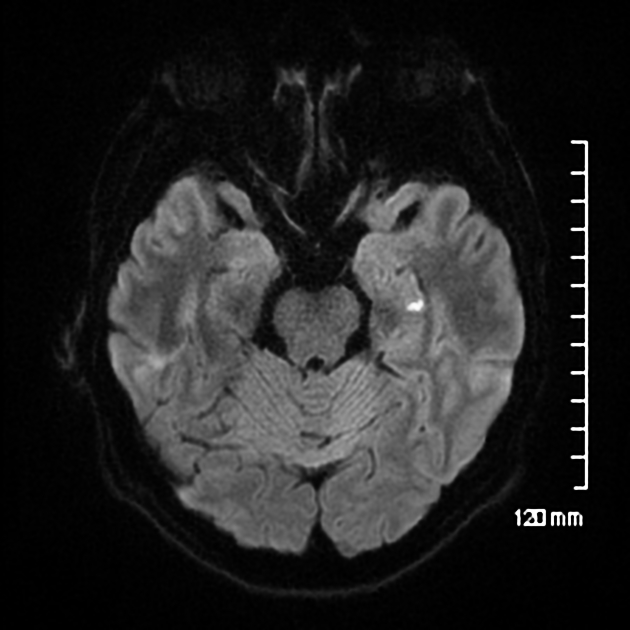

Research published in Frontiers in Human Neuroscience describes this as a disruption to hippocampal circuits that are critical for both encoding and storing memories.

Imaging confirmed temporary cerebral venous congestion caused by the Valsalva maneuver during each bathroom visit.